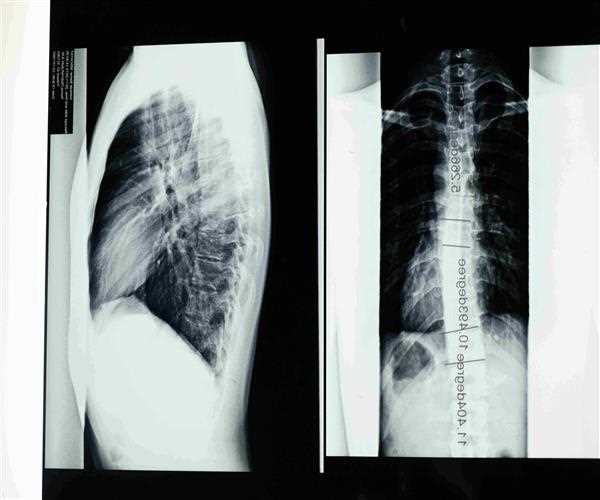

Because of the curvature of scoliosis, the spine resembles a letter 'C' or 'S' rather than a straight line down the middle of the back. They usually affect the upper and middle back (thoracic spine), although they can also affect the lower back.